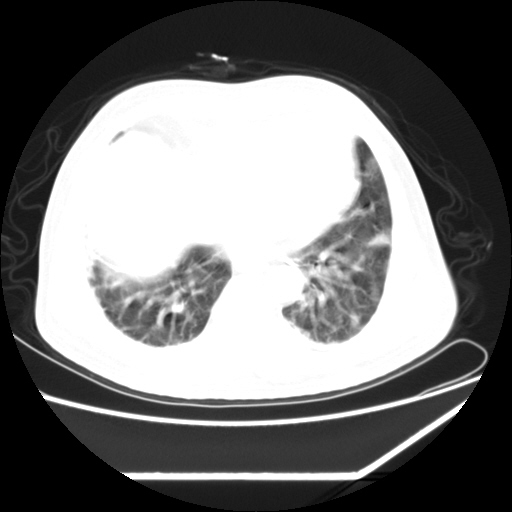

男,57,畏寒,发热

双肺多发结节样病灶,部分内见透光区,纵隔内见淋巴结肿大。结核临床如有畏寒,高热,白细胞增高首先考虑迁徙性肺脓肿(多是金黄色葡萄球菌感染)。

注意除外转移瘤。

1)考虑两肺感染性病变(金黄色葡萄球菌肺炎?);建议抗炎治疗后复查排除其他。2)双侧少量胸腔积液。

双肺典型的亚急性粟粒性肺结核

双侧胸膜结核